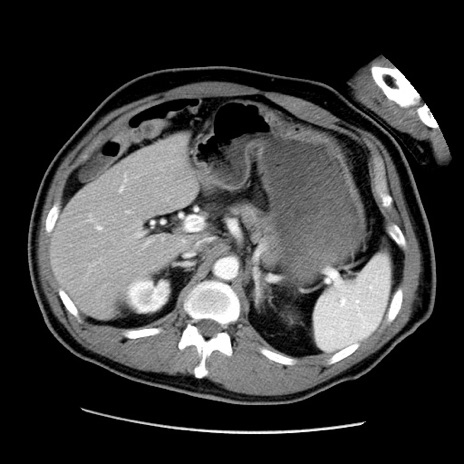

冠状断像

【症例】50歳代男性

【主訴】腹痛

【現病歴】AVMからの被殻出血のため回復期リハ病棟入院中。 本日午後3時頃急に下腹部痛が出現した。

【既往歴】AVM、被殻出血、虫垂炎、高血圧

【身体所見】意識晴明、左半身不全麻痺、会話の理解は良好、36.5°C、腹部:膨隆、全体に板状硬、下腹部正中に圧痛点あり、反跳痛-、筋性防御不明、右下腹部にope scar

【データ】WBC 9400、CRP 0.06